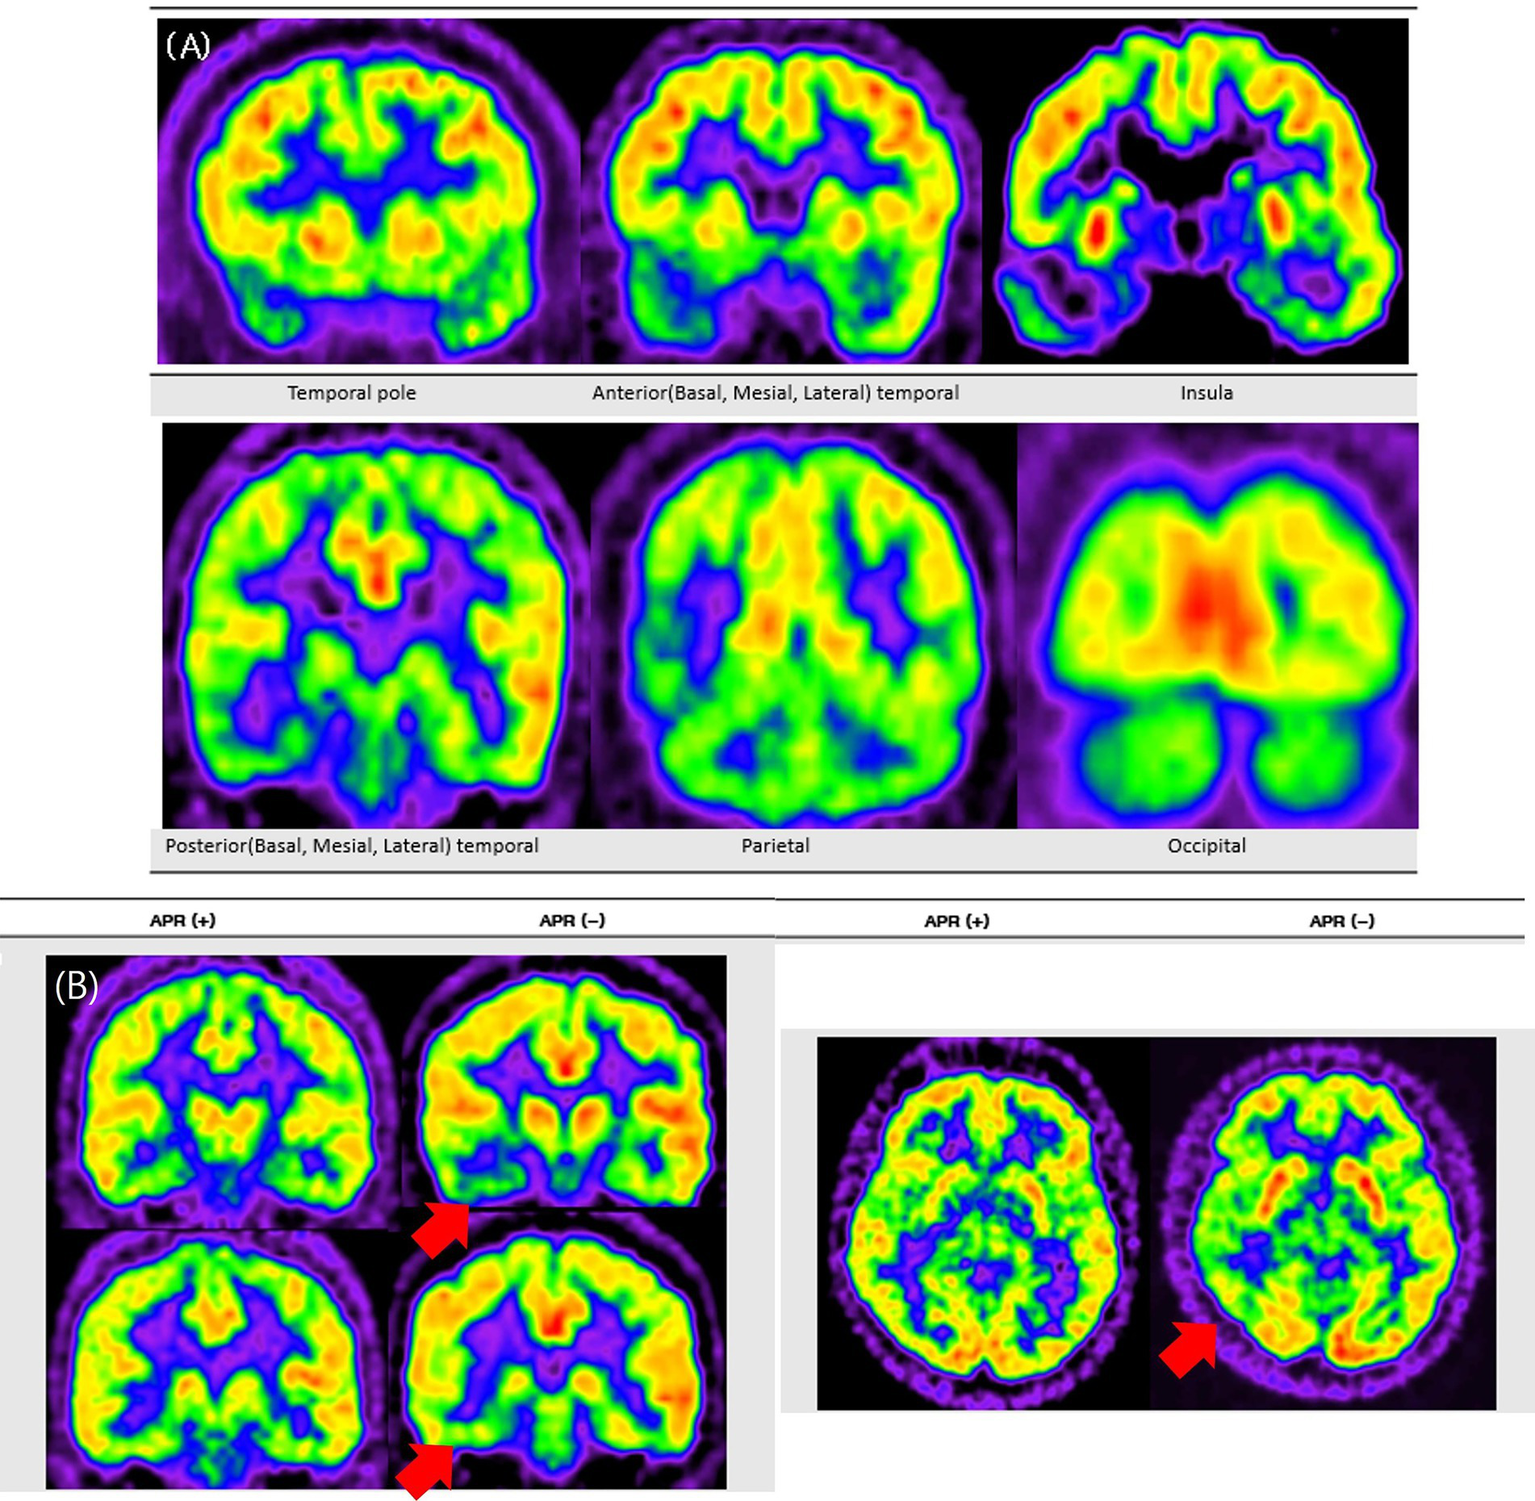

Visual analysis of PET images was conducted independently by three experienced epileptologists (H. B., Y. C., and Y. S.), who were blinded to all clinical data to minimize interpretation bias. The assessment of glucose metabolism followed a structured anatomical framework, encompassing both temporal and extratemporal regions (Figure 1). To ensure diagnostic accuracy and reliability, cases showing discordant interpretations among the three epileptologists and an additional imaging specialist underwent rigorous consensus review to establish definitive readings.

Figure 1

Topography of Anatomical areas assessed for regional hypometabolism on coronal FDG-PET images. This figure shows coronal schematic FDG-PET views outlining the anatomical areas evaluated for regional hypometabolism in the temporal lobe. It depicts anterior, posterior, mesial, lateral, and basal subregions that served as regions of interest in the analysis. The schematic provides spatial context for understanding how regional metabolism was assessed and compared across groups.

The temporal lobe was anatomically divided into anterior and posterior regions using the uncal apex as a landmark, with areas located anterior to the uncal apex classified as anterior and those posterior to it classified as posterior, in accordance with established anatomical criteria (5).